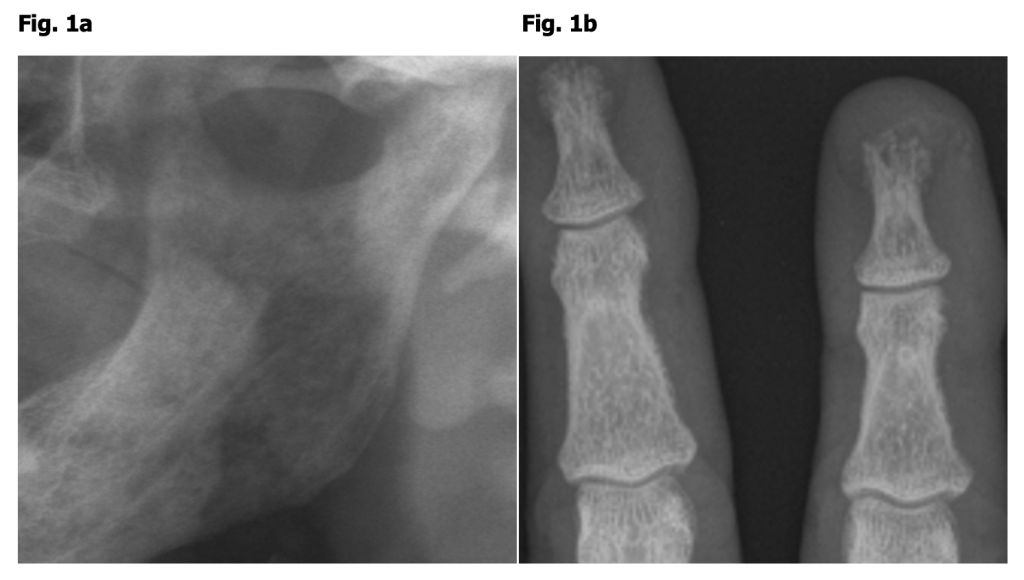

Figure 1: 57 y/o woman with left mandibular pain

a) Panoramic radiograph with sintered condyle.

b) Subperiosteal resorption of radial aspect of second and third middle phalanx, acroosteolysis.

Diagnosis: Hyperparathyroidism

If a temporomandibular condyle painfully collapses over months, we could simply keep it descriptive or call it “unspecific” necrosis (Fig. 1). If we go through old images, find kidney stones and a conventional X-ray of the hand, where subtle subperiosteal bone resorption of the radial aspect of the second and third middle phalanx have not been reported, we might be the first to hint to hyperparathyroidism.